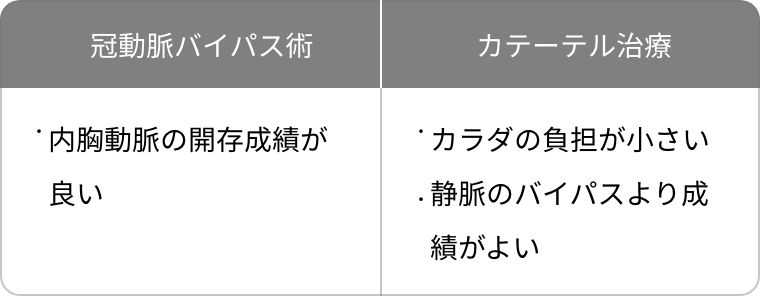

ハイブリッド治療とは本法のMIDCAB (低侵襲直視下冠動脈バイパス術)とカテ―テル治療の長所を組み合わせたものです。

冠動脈バイパス術の長所は、心臓の真ん中を走る一番大事な冠動脈(前下行枝)に内胸動脈をつなげることでカテーテル以上の良好な開存成績が得られる事です。しかし、体の真ん中を大きる切る正中切開法では、体の負担が大きくなってしまいます。一方、ステント治療は静脈を使ったバイパス術とは遜色ない結果であり、体への負担が小さい利点があります。

ハイブリット治療は両者の長所を活かした方法で、高齢者や正中切開が困難な方などには非常に有用な方法と考えております。